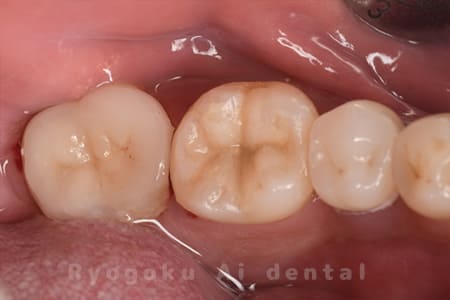

虫歯が大きく、保存不可能となった歯を上の親知らずと交換する自家歯牙移植を行いました。移植歯が小ぶりであったため、部分矯正を行い問題なく噛み合い、経過良好です。